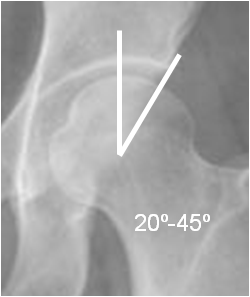

Mediciones importantes a la hora de valorar la patología de la cadera.

Fig 18. Angulo de cubrimiento lateral normal.

Rx AP de cadera.